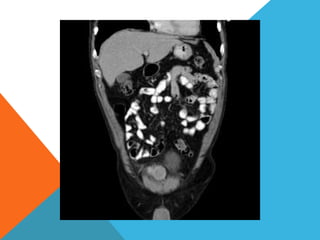

El paciente presentó síntomas de sangrado digestivo y pérdida de peso. Exámenes revelaron gastritis crónica asociada a H. pylori. Un tumor fue descubierto en una colonoscopia normal. La cirugía removió un tumor fibroide solitario, una rara neoplasia mesenquimal que usualmente crece lento y tiene bajo potencial de malignidad. El pronóstico después de la remoción quirúrgica es generalmente bueno.